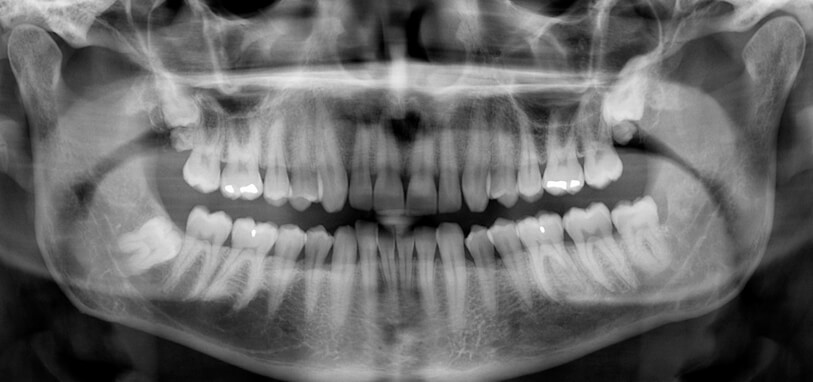

وی توضیح داد: میزان اشعه در رادیوگرافیهای دندانی بسیار پایین است؛ برای مثال، میزان اشعه در یک رادیوگرافی داخل دهانی معمولی حدود ۰.۰۰۵ میلیسیورت و تصویر پانورامیک (OPG) حدود ۰.۰۲ میلیسیورت است که به ترتیب هزار و ۲۵۰ برابر کمتر از حد مجاز ۵ میلیسیورت در دوران بارداری است.

وی تصریح کرد: در تصویربرداری پانورامیک دندان (OPG)، استفاده از محافظ تیروئید توصیه نمیشود.

وی توضیح داد که تابش پرتو از پشت سر بیمار انجام میشود و قرار دادن محافظ میتواند سایه در نواحی چانه، ریشه دندانهای قدامی یا فک پایین ایجاد کند؛ این موضوع کیفیت تصویر را کاهش داده و احتمال نیاز به تکرار عکس را افزایش میدهد که در نهایت میزان تابش اشعه را بالا میبرد.